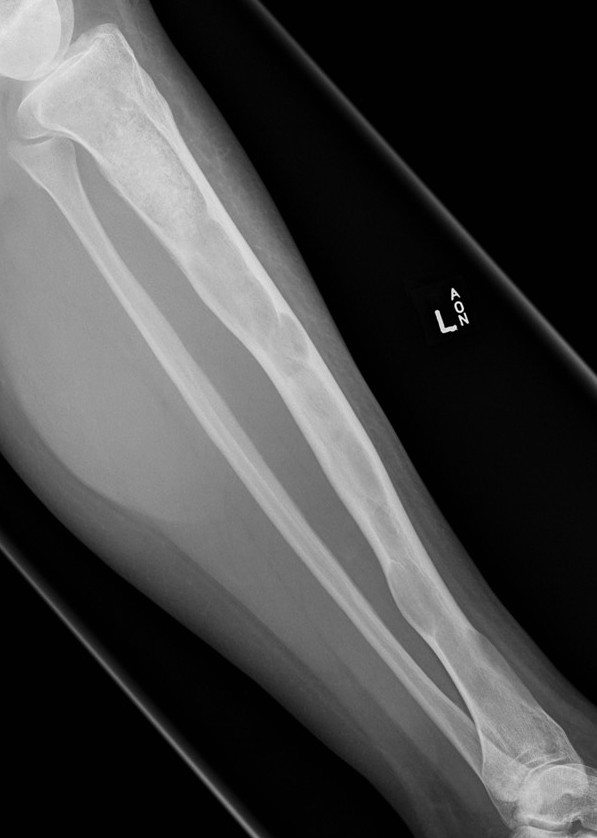

X-ray

Intramedullary lucent diaphyseal lesion with 'ground glass appearance'

- thinned, slightly bulged cortex

- ± endosteal scalloping

- may have angular deformity / bowing

Sabre tibia